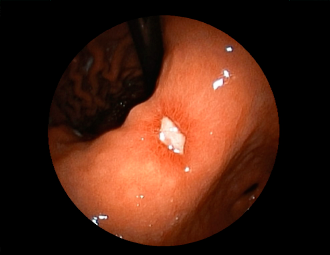

症例1:胃潰瘍(37才、男性)

①胃潰瘍(Stage A1)

健診:胃レントゲン検査で、胃角部ニッシェを指摘され当院受診。

胃角部小弯に、深くて大きな、大きさ約10mmの胃潰瘍(stage 1)

があり、潰瘍底は一部白苔はみ出しを認める。エソメプラゾールマグネシウム水和物投薬で治療開始しました。

(通常画像)